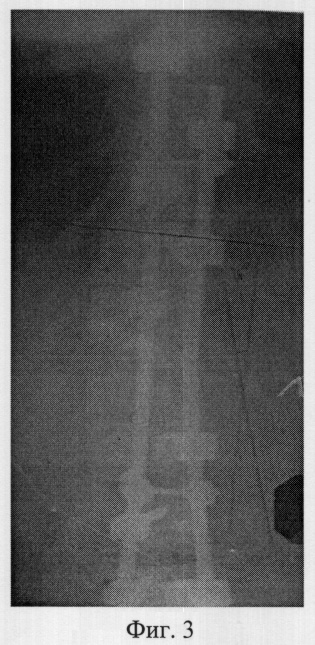

Фиг.3 – рентгенограмма в прямой проекции позвоночника больной К. после операции полисегментарной дорсальной коррекции и фиксации из заднего доступа транспедикулярными винтами;

По контрольным рентгенограммам в фасной (фиг.3) и боковой (фиг.4) проекциях, выполненных после операции, определили угол остаточной деформации по Кобб 16°, степени коррекции 57°, что соответствует 78% от первоначальной деформации.